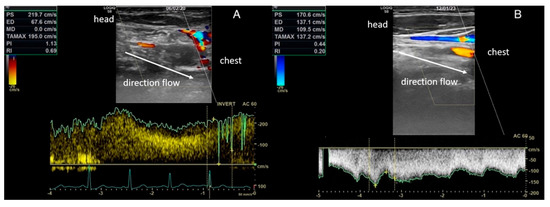

2.4. Vascular Assessment